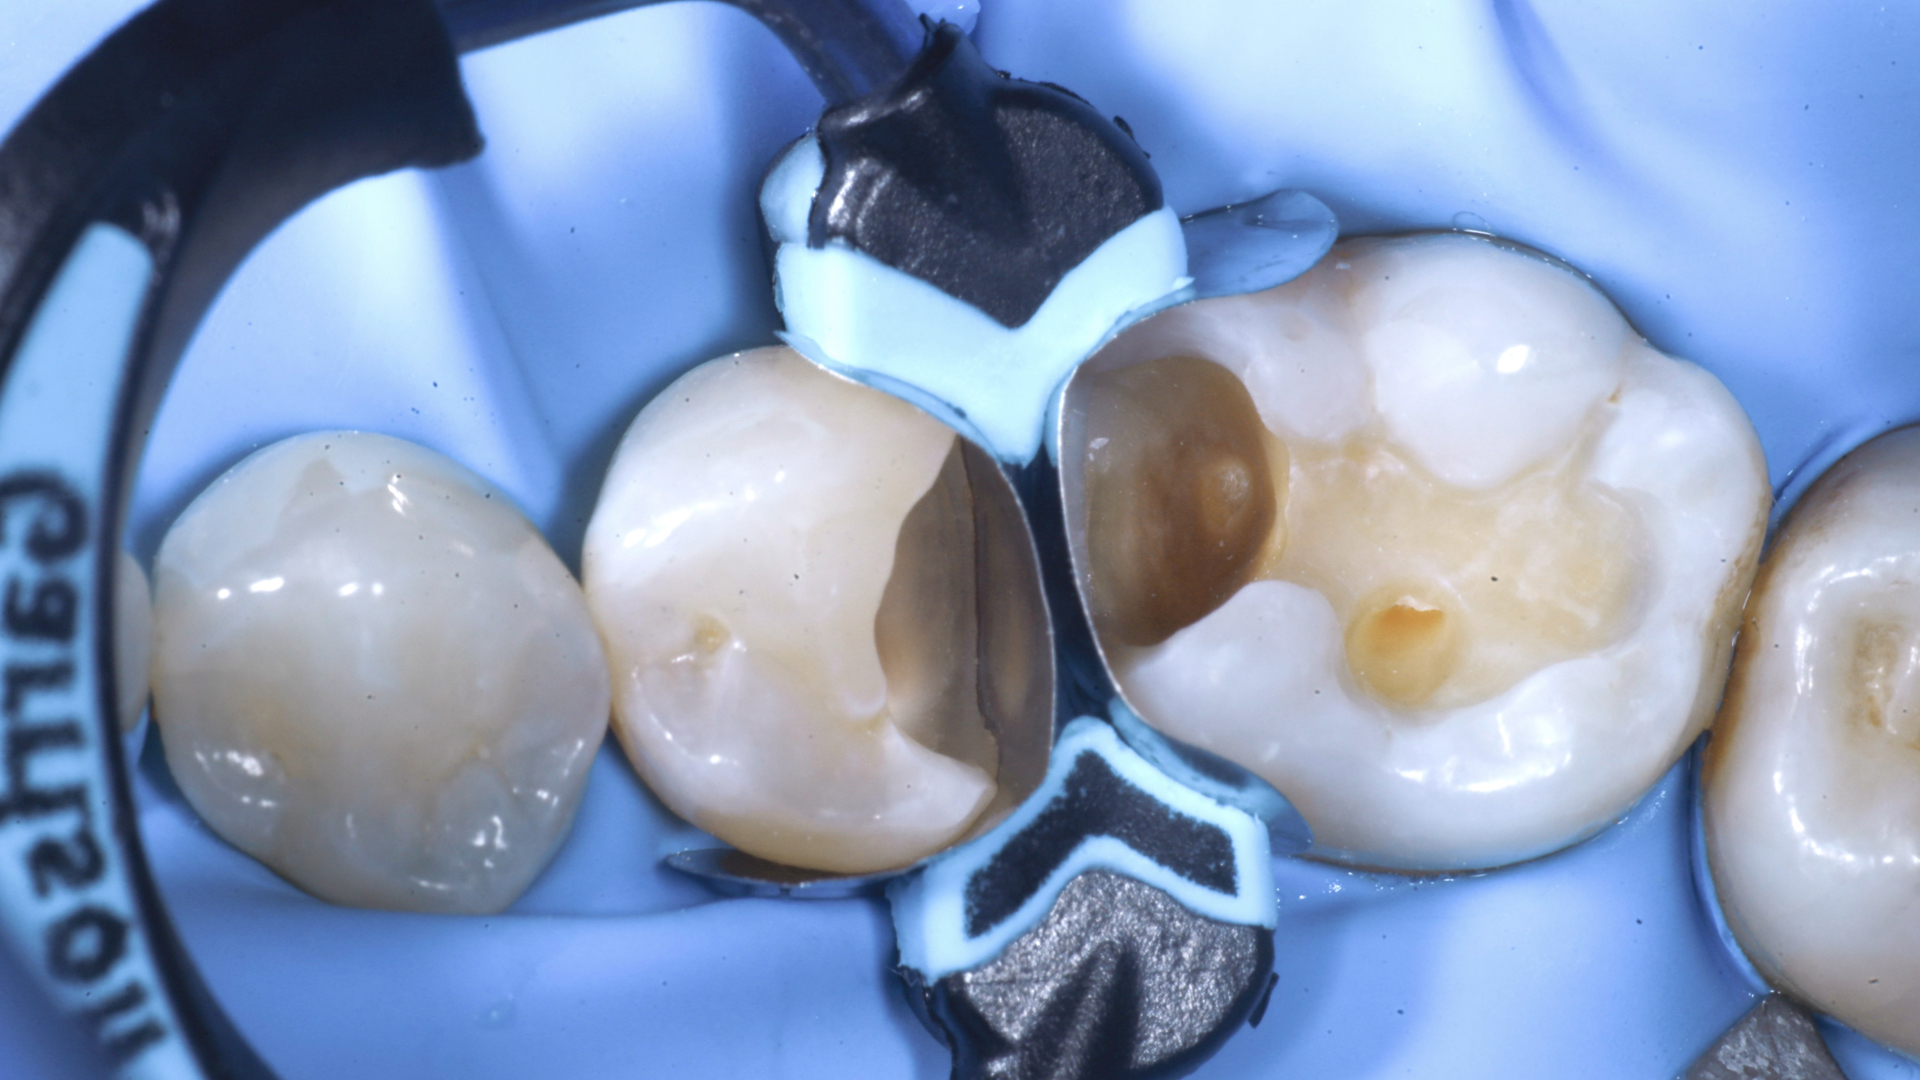

Verifica fotografica del sigillo cervicale distale a 2.5 Creazione della parete inter-prossimale distale a 2.5, eliminazione della matrice e successivo inserimento del cuneo d dell’apposito anello con una sola attrice mantenuta